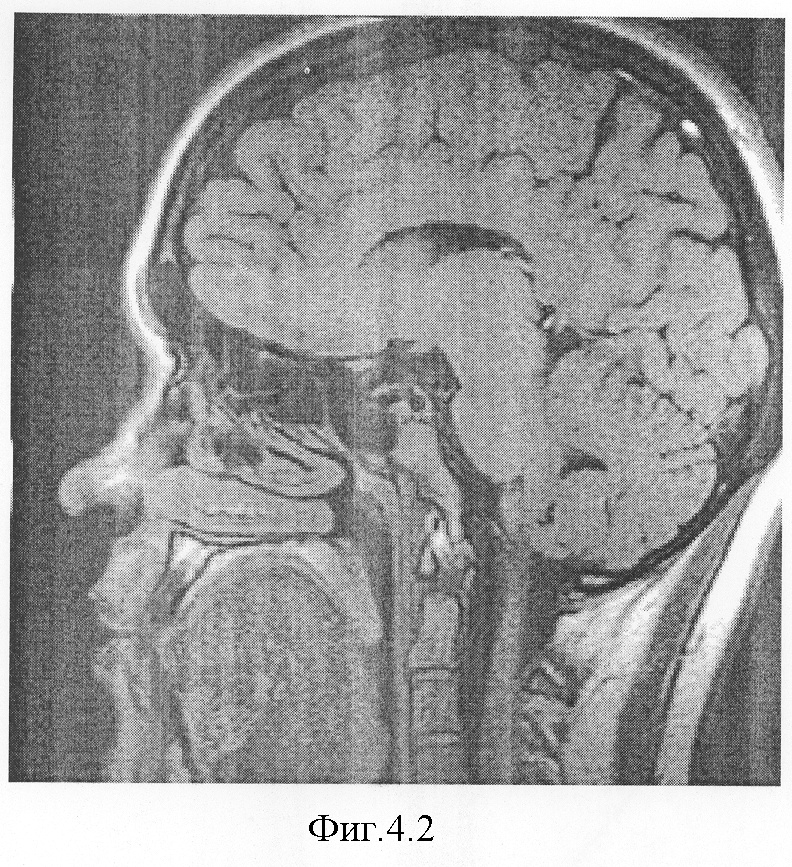

На фиг.4.1-7 показаны результирующие семь изображений, проходящие в сагиттальной плоскости через гипофиз. При этом фиг.4.1 проходит в непосредственной близости от турецкого седла справа, через сифон внутренней сонной артерии, гипофиз не затрагивает;

фиг.4.2 проходит через край турецкого седла и также не затрагивает гипофиз, а поэтому площадь сечения не обводится;